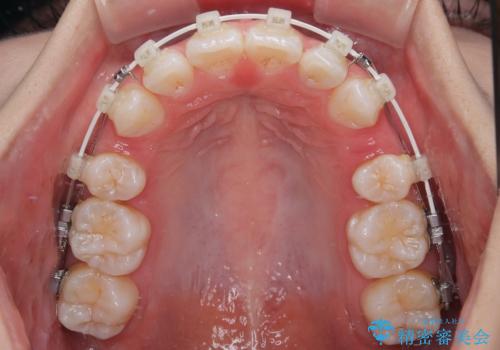

- 矯正装置

- 審美装置

- 治療計画

- 口を閉じたときに飛び出してしまう上顎前歯を気にして来院された患者様です。

下顎はデコボコが気になっていたため、上下左右第一小臼歯4本を抜去して、ワイヤー装置にて口元の突出感を改善するよう矯正治療を行うこととしました。